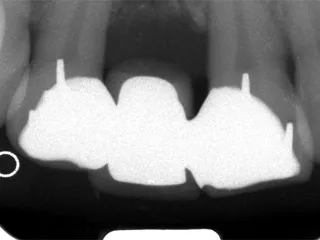

ピンレッジ・レントゲン写真 レントゲン写真